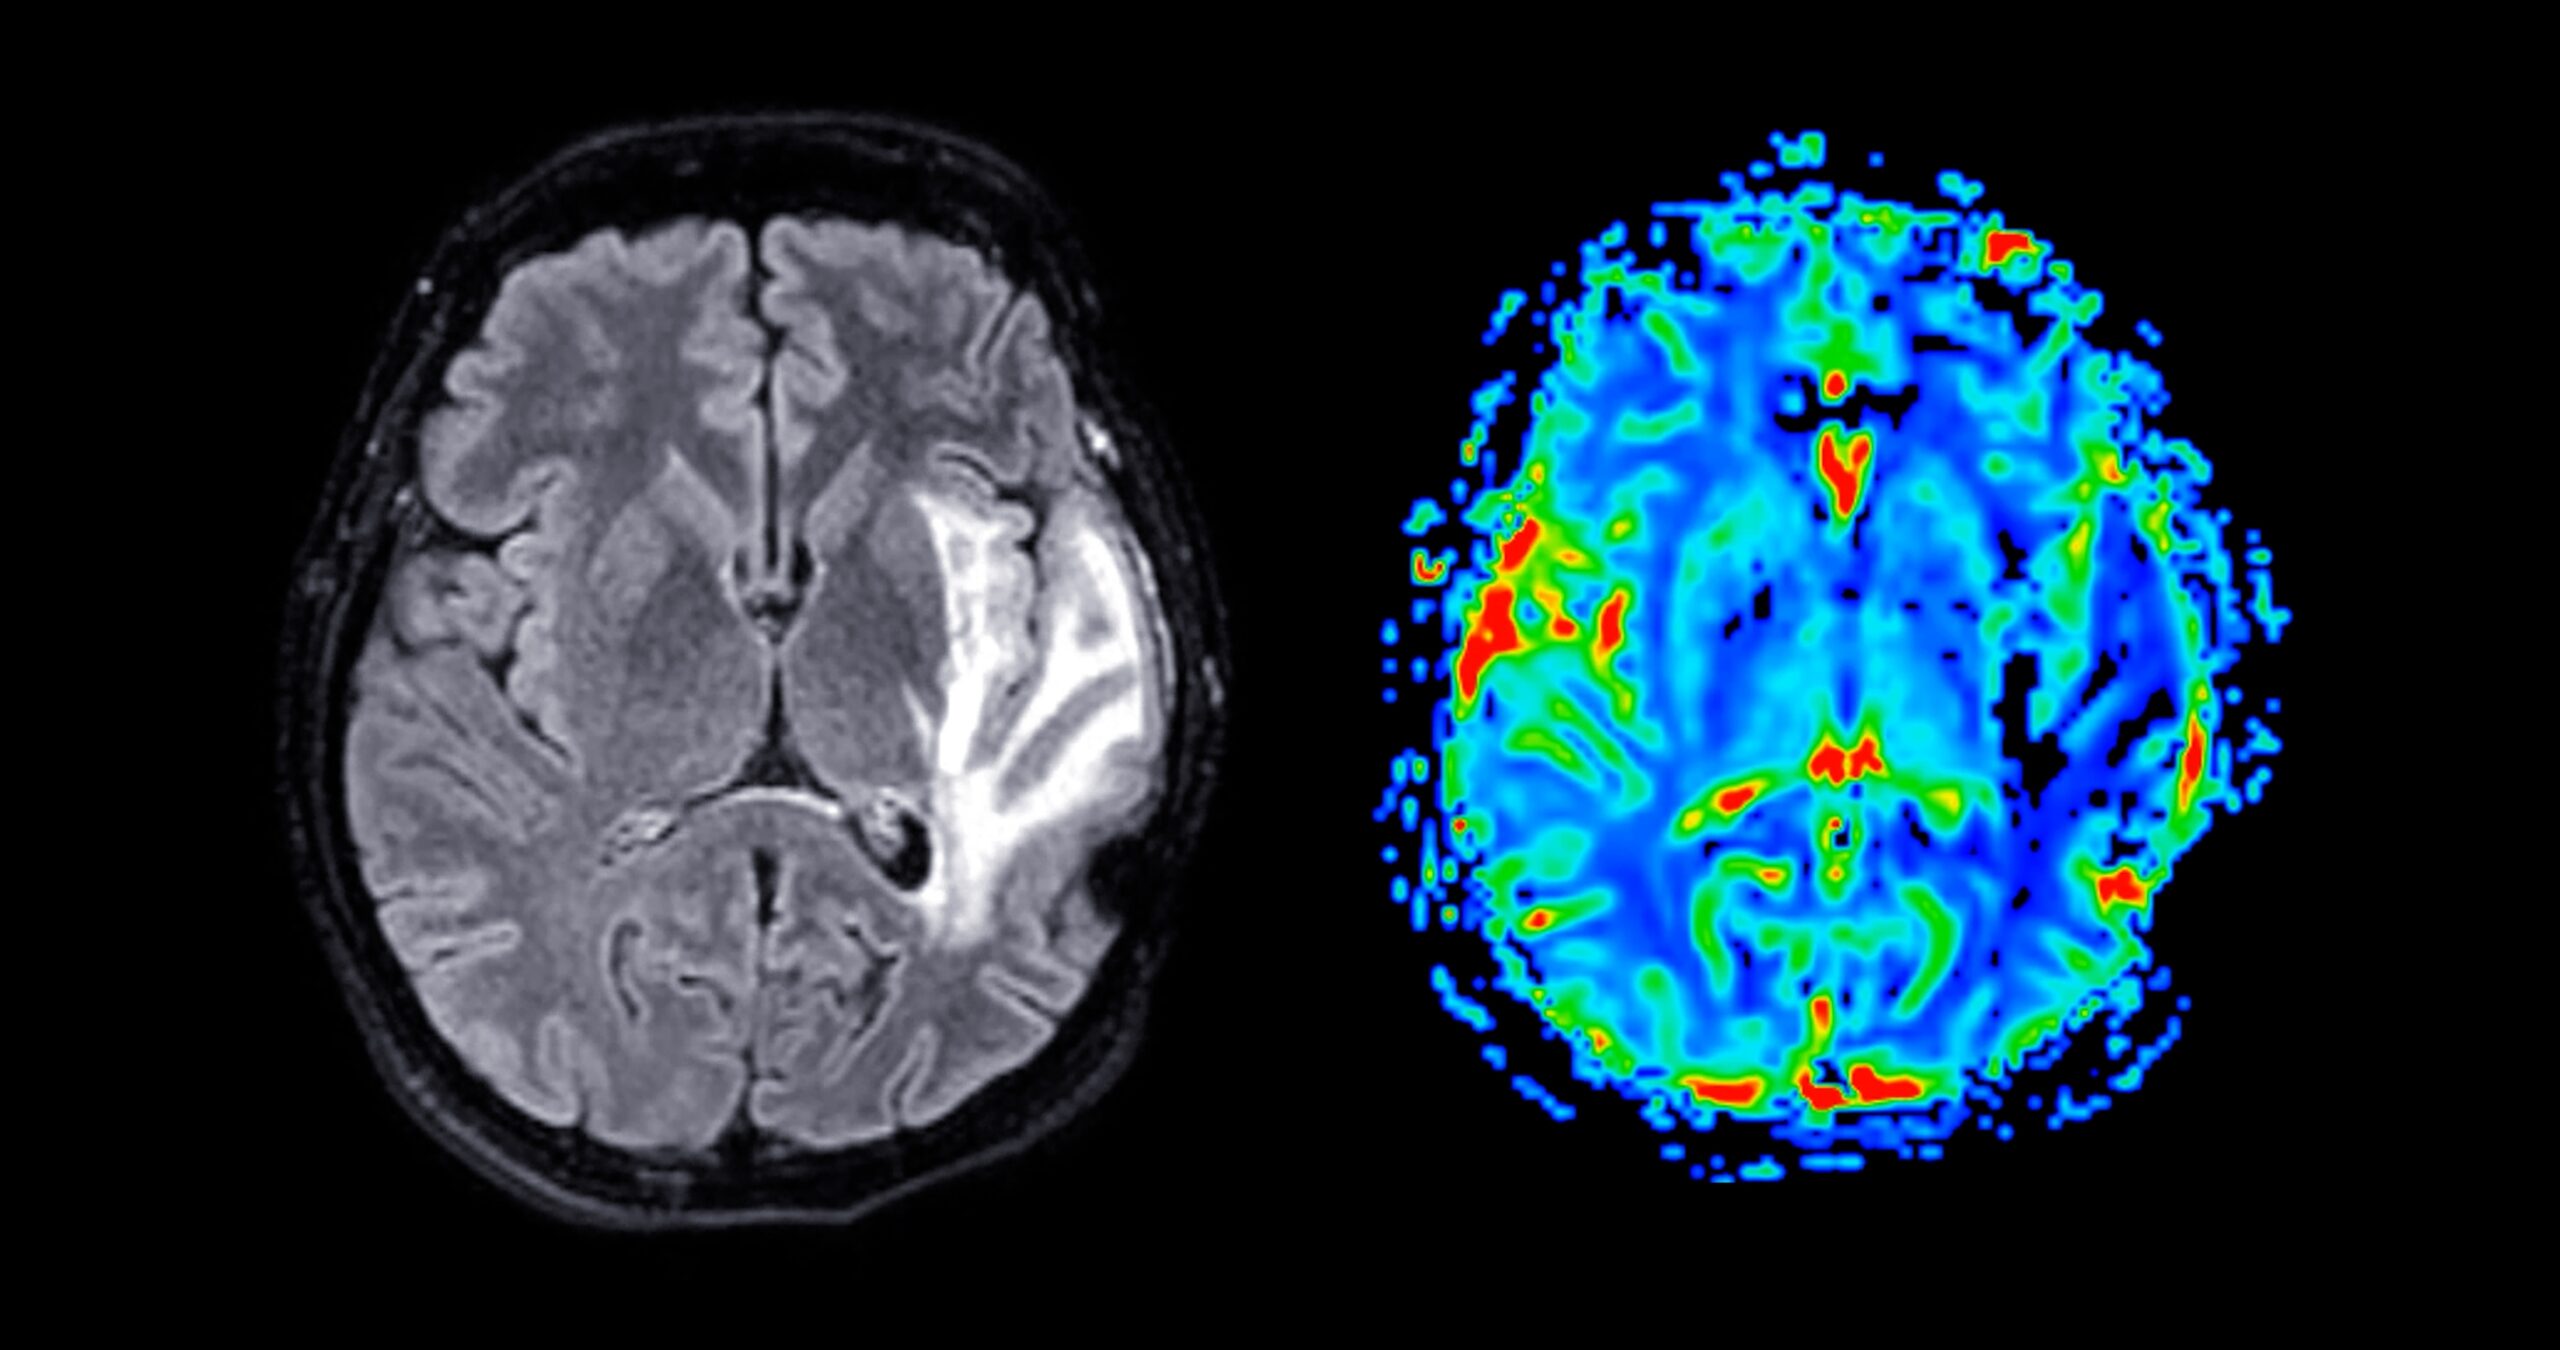

The findings are not a diagnosis but suggest more than 1 million older people could meet NHS criteria for anti-amyloid treatments, far higher than previous estimates of 70,000. Researchers analysed blood samples from nearly 11,500 randomly selected people using a p-tau217 biomarker test that can detect Alzheimer’s-related changes early.

Published in Nature, the study found these changes become more common with age, rising from under 8% in people in their 50s and 60s to about two-thirds of those over 90. Experts say the results could transform early detection, though current treatments remain costly and are not widely available on the NHS.